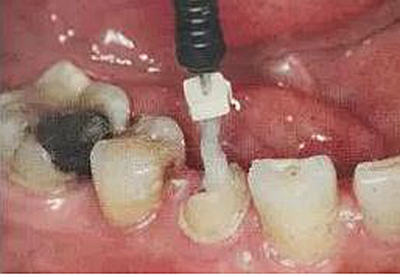

3、樁道預(yù)備

用P鉆從1號(hào)到4號(hào)逐級(jí)擴(kuò)大根管,如果根管是大錐度預(yù)備,可以省略1號(hào)。在預(yù)備之前要測(cè)量長(zhǎng)度,將最終預(yù)備的長(zhǎng)度用皮圈標(biāo)記在鉆針上。用1號(hào)P鉆時(shí)尤其要小心,是最容易斷的,用的時(shí)候要注意手法。

每個(gè)品牌的纖維樁都會(huì)有配套的鉆,在用P鉆預(yù)備后就應(yīng)該用廠家的鉆了,纖維樁預(yù)備時(shí)不用去除根管內(nèi)壁上的倒凹,只要保證足夠的長(zhǎng)度和直徑即可。

隨后還要用P鉆預(yù)備,將根管內(nèi)壁上完全清理干凈,殘留的任何一點(diǎn)東西者會(huì)影響粘接效果。